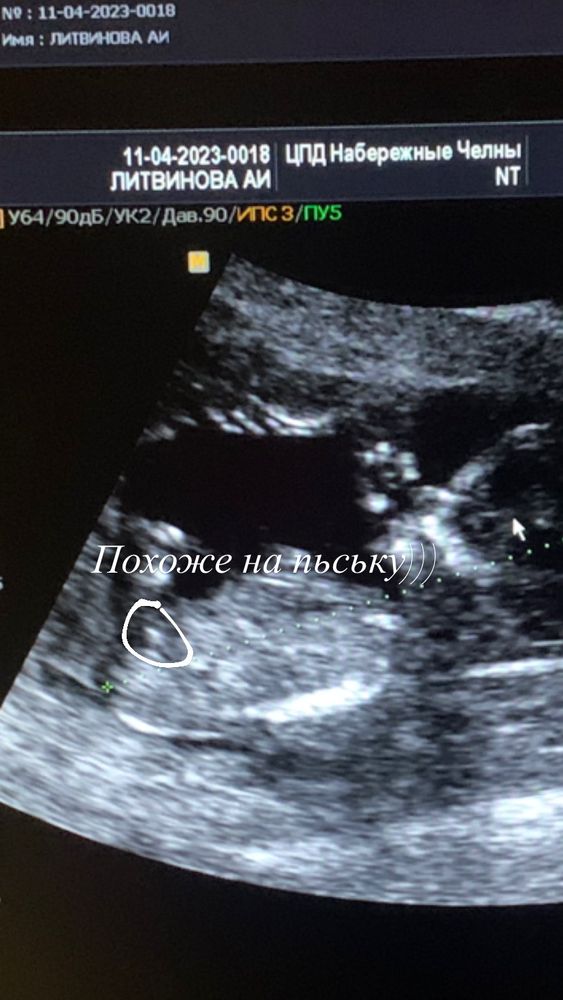

Пол плода на 11,6 недель

На первом скрининге попала к молодому специалисту, пол мне не предположили( По снимку можно что-то увидеть?

Пол смотрят по другой проекции. Тут не видно. Но я интуитивно предположу, что это мальчик)